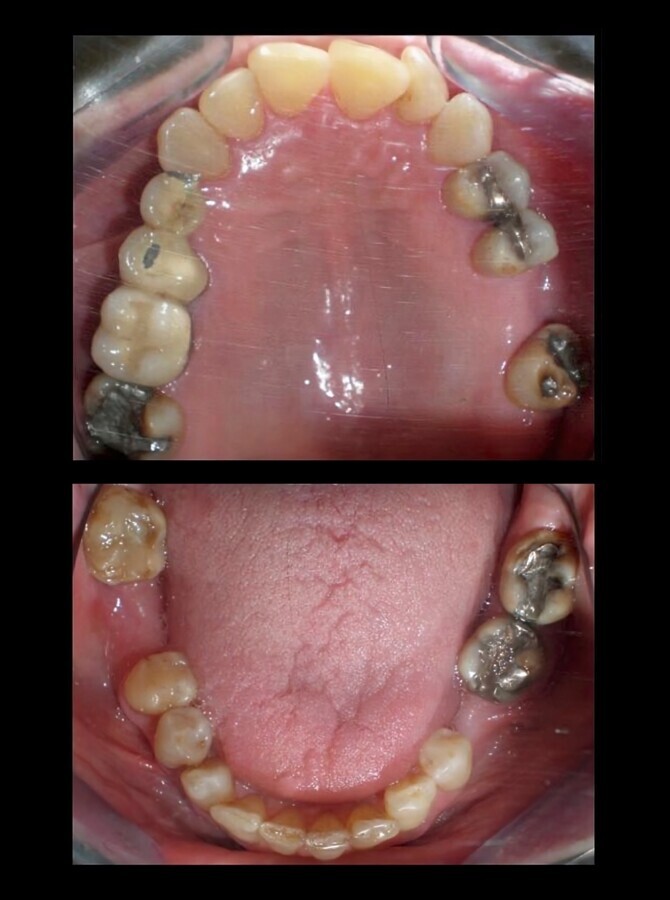

El tratamiento dental de los pacientes que sufren de cáncer depende del estado de su salud oral, que puede ser deficiente, como en el caso del paciente bajo tratamiento con tamoxifeno (1), en estado de salud oral aceptable, como en el paciente siendo tratado con el mismo medicamento (2) o en buen estado de salud oral, en el caso de un paciente con cáncer de colón (3).

2. b) Mal estado bucal (higiene pobre, enfermedad periodontal grave, y más de 20 caries) (Figura 1).

Figura 1. Paciente de 60 años, en mal estado de salud oral, y en tratamiento con tamoxifeno. En estos pacientes puede ser aconsejable realizar una edentación total.

1. c) Estado bucal regular (no enfermedad periodontal grave, menos de 20 caries e higiene regular) (Figura 2).

Figura 2. Paciente de 66 años de edad, en estado de salud oral aceptable, y en tratamiento con tamoxifeno. Se debe concienciar al paciente sobre higiene oral, hacer aplicación de flúor y tratamiento conservador de aquellos dientes que puedan ser restaurables.

1. d) Estado bucal bueno (Figura 3) (no enfermedad periodontal, caries casi ausentes y buena higiene).

Figura 3. Paciente de 65 años de edad, en buen estado de salud oral, con antecedentes de cáncer de colón tratado a los 61 años. Se debe concienciar al paciente sobre higiene oral, hacer aplicación de flúor y tratamiento conservador de aquellos dientes que puedan ser restaurables, cirugía preprotésica y periodontal, eliminar prótesis metálicas si se va a recibir radioterapia.